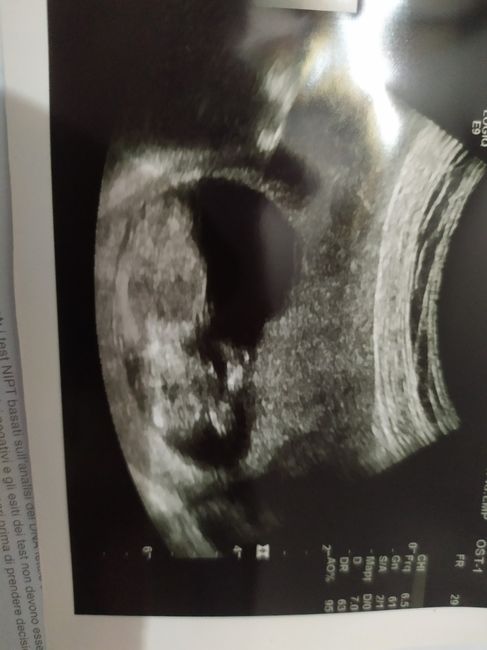

Tra 10 GG avremo i risultati e speriamo bene...mentre giovedรฌ faremo i bitest๐ค๐ค๐ค๐ค๐ค๐ค.....ed a voi come procede